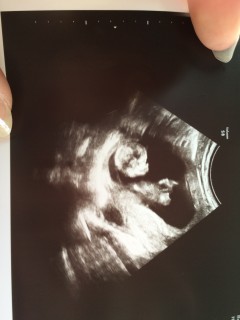

CRL68.1でした。まだ悪阻も少し残っていますが、今のところ順調で育ってくれていて嬉しいです。性別はまだ全然わからないって言われました。早く知りたいです笑

約7cm、週数相当で元気に動いてくれていました!もともと痩せ体系ですが、2ヶ月近く継続中のつわりで体重が4キロ落ちて、とうとうBMIが16を切ってしまい、体重要管理になってしまいました…。なのでまだ2週間隔の検診です(笑)にも関わらずお腹の赤ちゃんは順調に育ってくれているので、つくづく女性の身体って凄いなぁと思います。先生には目標臨月までにプラス15kgと言われてるので、赤ちゃんとともに頑張ります(笑)

初めて経腹エコーでした。2週間前は45.4㎜だったのが今回は75㎜に成長していました。 終始クルクルまわったり手足をばたつかせていました。元気な姿が見れて良かったです。

分娩先の病院にて、初回の妊婦検診でした。 9wの時にエコー画像に結構分厚い浮腫が見られてかなり不安でしたが、今日の検診では医師からも特に指摘も無く、エコーを見た所浮腫も無くなっているようでした。 頭からお尻まで7.2cmで、ちょうど平均値の真ん中だと言われました。 小さ過ぎず大き過ぎず、ちょうど良いですね、とのことで一安心。 診療ノートには【胎動活発】の文字が。 すくすく育ってほしいです。